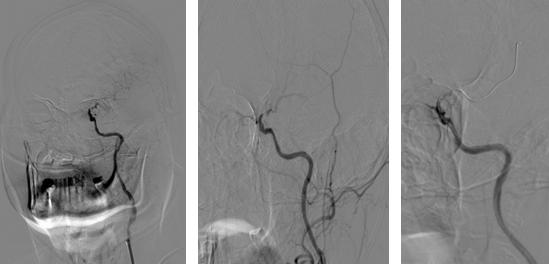

(术前造影左侧颈内动脉C6段次全闭塞血流缓慢)